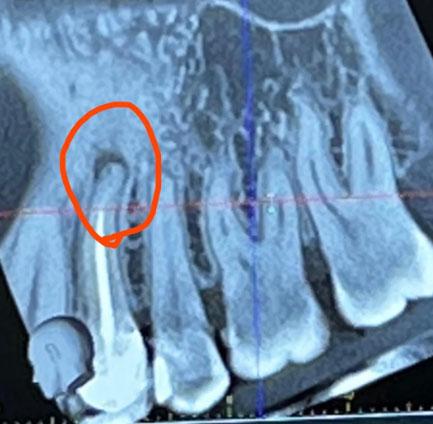

Apical Infection After Root Canal - CBCT Dental Case

Dental Case Analysis – Apical Infection After Root Canal Treatment

This CBCT image shows the anterior maxillary region with multiple natural teeth. A well-defined radiolucent lesion is visible at the root apex of a previously treated tooth (circled area), indicating a persistent apical infection. Surrounding bone shows early structural changes.

Clear apical radiolucency at root tip

Loss of normal bone trabeculation

Root canal filling present but likely incomplete

Lesion confined but expanding

Adjacent teeth currently unaffected

Chronic apical periodontitis

Failed or compromised root canal treatment

Localized periapical bone loss